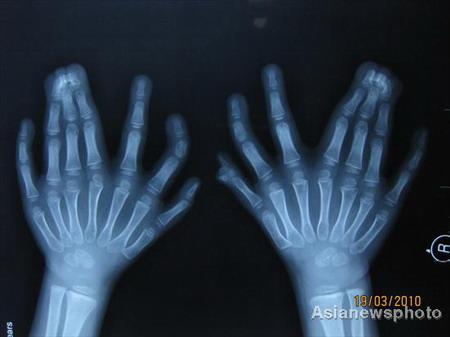

Маленькому китайцу удалили 11 лишних пальцев

Китайские хирурги из города Шэньян провели операцию по удалению лишних пальцев у 6-летнего мальчика. После сложной ампутации ребенок чувствует себя хорошо…

До операции малыш обладал самым большим в мире количеством пальцев…

Ребенок появился на свет с 31 пальцами – 16 на ногах…

…И 15 на руках…

По словам врачей, такая особенность малыша вызвана генетическим заболеванием, которое известно медикам под названием «полидактилия»… Оно передается по наследству либо возникает в случае непрогнозируемой мутации генов.

Обычно в результате этого заболевания у пациента имеются лишние пальцы, выросшие рядом с мизинцем, однако данный случай квалифицируется врачами как «центральная полидактилия», в рамках которых продублированы средние пальцы.